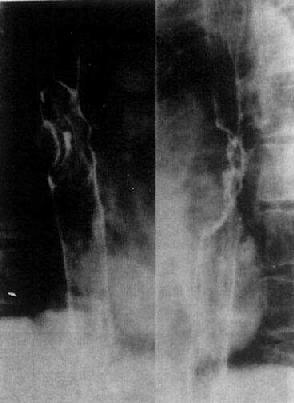

食管癌的X线表现可概括为以下几点(图4-2-9):①粘膜皱臂消失、中断、破坏,代之以癌瘤表面杂乱不规则的影像;②管腔狭窄,在典型浸润型癌,肿瘤表现为环状狭窄,狭窄范围一般局限,为3~5cm,边缘较整齐,与正常区分界清楚。钡餐通过受阻,其上方食管扩大。管腔狭窄也见于各型食管癌的进展期,范围常较大,轮廓不规则、不对称,管壁僵硬;③腔内充盈缺损,癌瘤向腔内突出,造成形状不规则,大小不等的充盈缺损,是增生型癌的主要表现(图4-2-9);④不规则的龛影,见于溃疡型癌,可见一个较大、轮廓不规则的长形龛影,其长径与食管的纵轴一致,周围不规则的充盈缺损。向食管壁内或管外生长的肿瘤可形成纵隔内肿块影。

图4-2-9 食管癌(增生型)食管中段显示不规则

充盈缺损,粘膜破坏,管腔狭窄